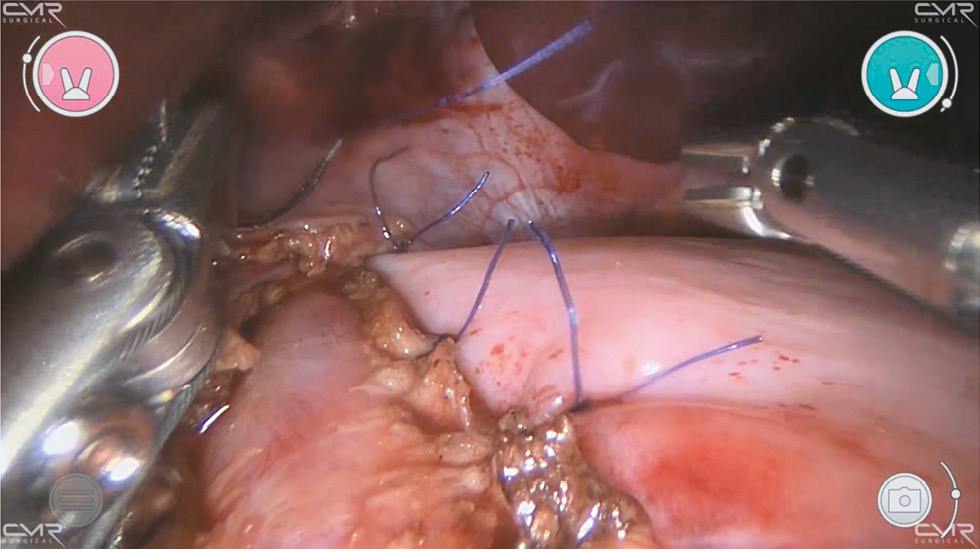

Процедура начинается с рассечения френоперикардиальной связки. Короткие желудочные сосуды не лигируются. Идентифицируются и сохраняются передний и задний блуждающие нервы. Продольную миотомию выполняют с помощью электрохирургического крючка, начиная с желудочно-пищеводного перехода и продвигаясь вверх на 5 см, затем продолжают разрез вниз на 2 см в сторону угла желудка (рис. 2).

Рис. 2. Роботизированная миотомия Хеллера: этап продольного рассечения мышечного слоя пищевода.

Fig. 2. Heller robot-assisted myotomy: the stage of longitudinal dissection of muscular layer of the esophagus.